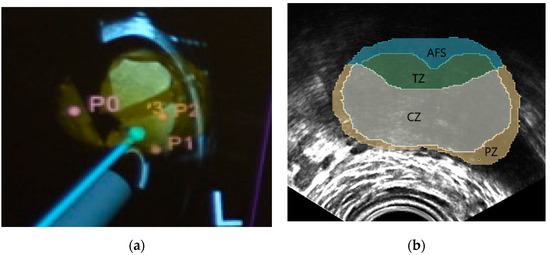

NaviPBx guides the physician with real-time “labels” painted over the live 2D TRUS image, such as in Figure 4a, showing models of the TRUS transducer (grey), biopsy needle (magenta), prostate gland (yellow) and biopsy target locations (pink), that are overlaid on the live 2D TRUS image. The physician interfaces with NaviPBx through a lightweight user interface optimized to execute only the necessary workflow while hiding all other functions. The system records all intra-operative data (e.g., time-stamped ultrasound, tracker, video, audio, rendering scenes, user actions, and internal variables) for offline analysis and validation when the user interface is turned back on at full functionality.

Labeling the McNeal zones (central, transition, peripheral and anterior zones) in TRUS is a critical function for planning and sampling the systematic biopsy target locations, typically 12 cores [7]. For this purpose, we plan to reuse our previously developed implementation. Our current prototype starts with a set of anonymized labeled prostate MRI volumes, with segmentations of the prostate and the McNeal zones. Having segmented the prostate in 3D TRUS, we select the MRI scan with the most similar prostate, based on statistical shape analysis, then perform a deformable elastic registration between the prostate glands in the selected MRI and the 3D TRUS, with an existing module (e.g., BRAINSFit) of 3D Slicer. Finally, we apply the resulting deformation field to map the McNeal zones onto the 3D TRUS, and then paint the McNeal zones on the live 2D TRUS image, such as in Figure 4b. In a preliminary experiment with seven expert urologists, this module correctly labeled the McNeal zones 92% of the time, mislabeling only the central zone where very few prostate cancers start [26]. We expect occasional mislabeling to disappear when we use a larger set of model-training MRI volumes, including a pool of patients with advanced disease. Over 80 anonymized labeled MRI/TRUS volume pairs are currently available to us for this purpose, from previous research. It must be noted that the most important aspect is the correct labeling of the McNeal zones, while the metric accuracy required for the zonal contours is quite lenient, considering the smallest size of significant prostate cancer to be biopsied, 0.5 cc in volume [11]. Altogether, this prostate anatomy labeling prototype module promises clinically sufficient performance when fully integrated in NaviPBx.

Figure 4. Typical system guidance views of the NaviPBx prostate biopsy system. (a) Models of the TRUS transducer (grey), biopsy needle (magenta), prostate gland (yellow), and the biopsy target locations (pink), that are overlaid on the live 2D TRUS image. (b) McNeal zones painted on the live 2D TRUS image.